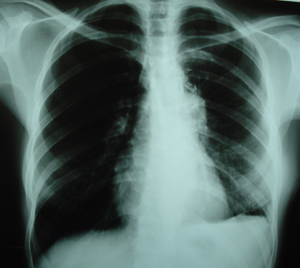

Εικόνα 1

Οπισθιοπροσθία ακτινογραφία θώρακος. Διακρίνεται διεύρυνση του μεσοθωρακίου που οφείλεται στην ύπαρξη όγκου στο μεσοθωράκιο.